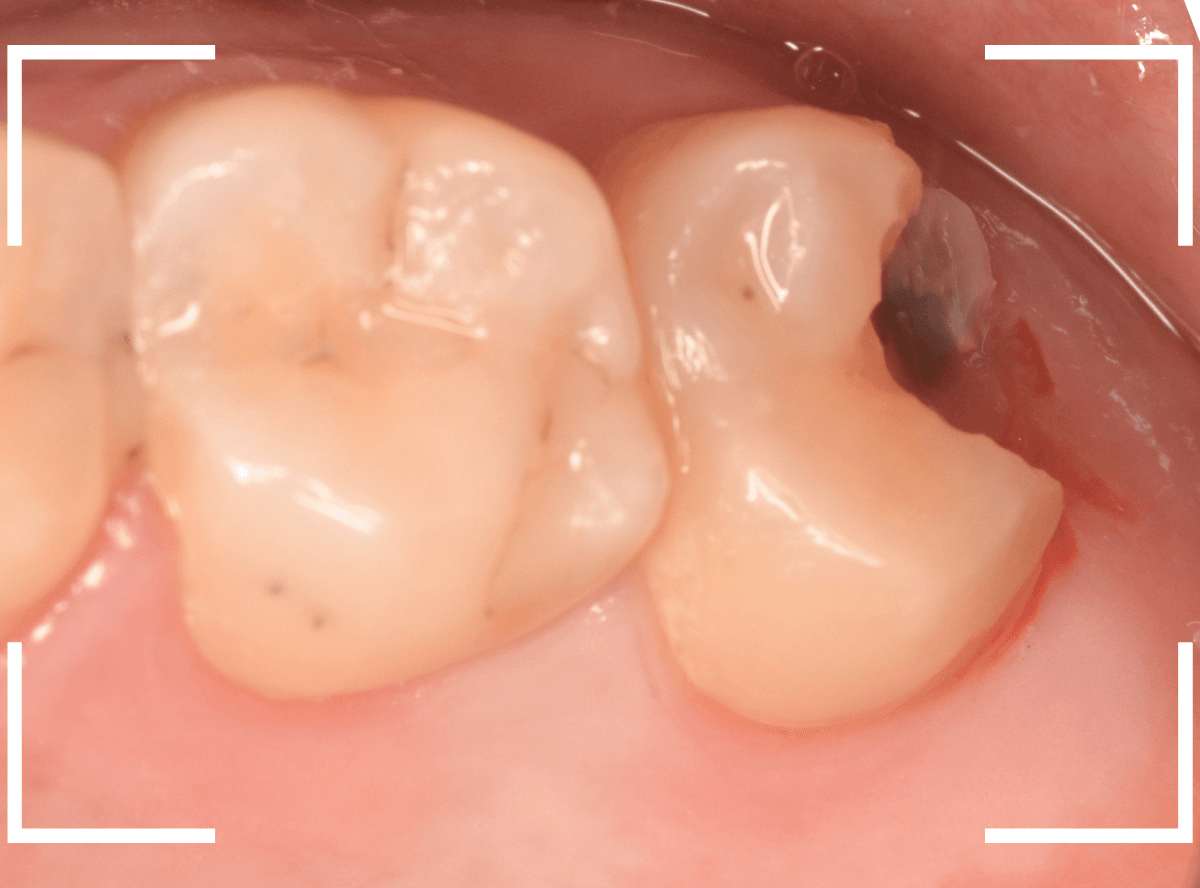

抜歯してしばらく経ったところです。

特に問題なさそうに見えますが、「おやしらずを抜歯してから、歯がしみるようになった」との訴えです。

これは、おやしらずを抜歯した後によくある症状です。